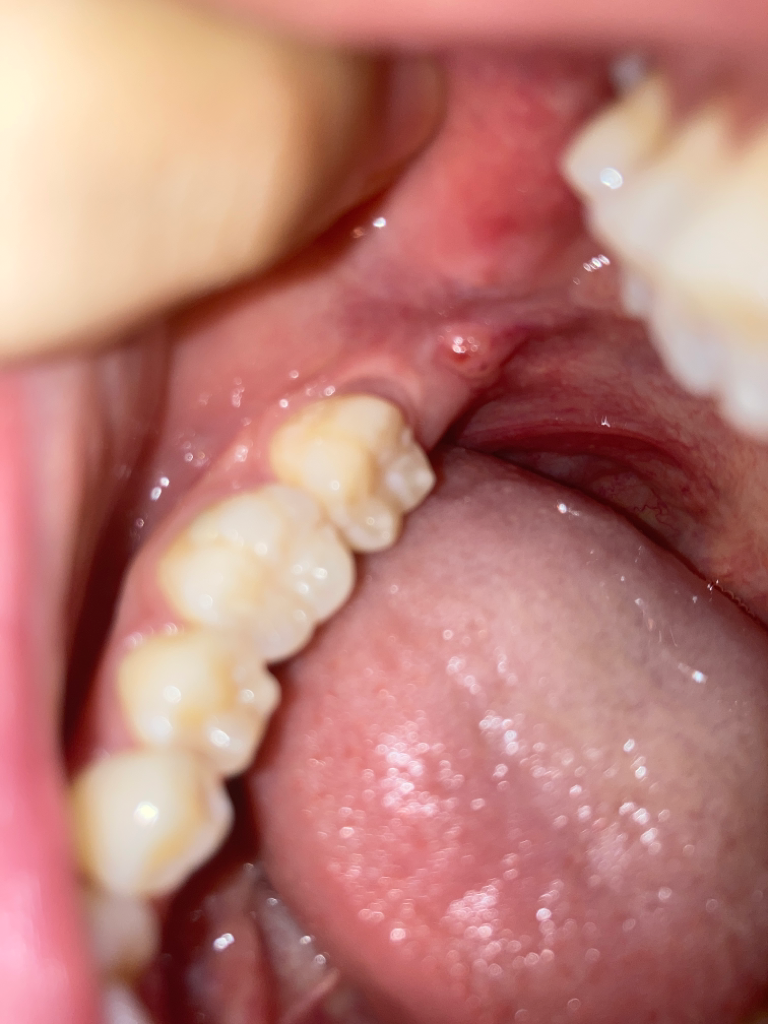

사랑니 근처이고, 씹히는 부분 근처인데 직접적으로 씹히진 않아요 혹 위로 빨갛게 피가 고인 것처럼 보이고 뒤에 하얀 점(구내염 같은)이 있어요... 구내암은 아니겠죠 20대 초반입니다 너무 불안해요

• 2번 째 사진

아마도 구내염으로 추정되는 병변입니다. 구강암의 양상과는 차이가 있으니 안심하시고 이비인후과 내원하셔서 적절한 치료를 받는 것을 권유드립니다.